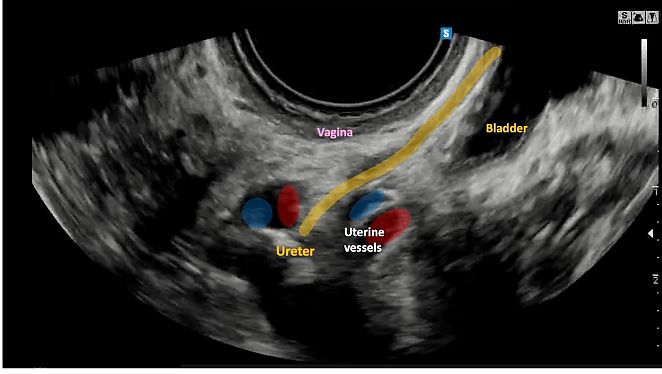

The anterior parametrium is defined as the space bounded anteriorly by the bladder and laterally by the terminal part of the ureters (i.e. the section between the crossing point with the uterine artery and the bladder inlet) (Figure 6).13

6

Longitudinal view of the anterior parametrium.

The lateral parametrium (or paracervix, or paracolpium), corresponds to the area located between the cervix and the lateral pelvic wall.13 This region contains lymphovascular structures (i.e. uterine artery, superficial uterine vein, umbilical artery, external iliac vessels) and is divided into medial and lateral parts by the ureter, which is located centrally within this area.13

During ultrasound examination, the lateral parametrium can be assessed by placing the probe in the posterior vaginal fornix to visualize the midsagittal plane of the uterus. The probe can then be moved laterally towards the pelvic sidewall until the iliac vessels are visualized, providing a longitudinal view of the ureter and uterine artery. By rotating the probe 90°, with a transverse section of the ureter visualized in the middle, the medial extension of the lateral parametrium (i.e. from the cervix to the ureter) and a lateral extension of the lateral parametrium (i.e. from the ureter to the iliac vessels/pelvic wall) can be studied (Video 9).